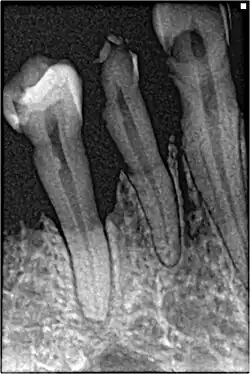

If disease is identified through this process, then a full periodontal analysis is performed, often by dental hygienists, oral health therapists, or specialist periodontists. This involves full mouth periodontal probing and taking measurements of pocket depths, clinical attachment loss and recession. Along with this other relevant parameters such as plaque, bleeding, furcation involvement and mobility are measured to gain an overall understanding of the level of disease. Radiographs may also be performed to assess alveolar bone levels and levels of destruction.[40]

In periodontal health, the alveolar bone surrounds the teeth and forms the bony socket that supports each tooth. The buccal and lingual plates and lining of the sockets are composed of thin, yet dense compact or cortical bone.[3] Within the cortical plates and dental sockets lies cancellous bone, a spongy or trabecular-type bone which is less dense than compact bone.[6] The anatomic landmarks of the alveolar process includes the lamina dura, the alveolar crest, and the periodontal ligament space.[9]